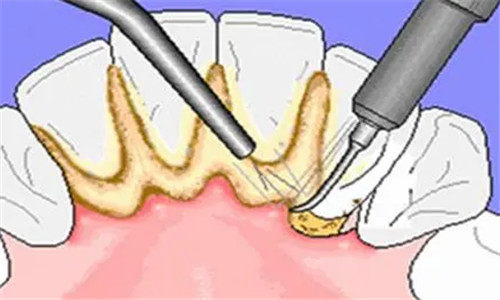

中浩口腔提供超声波洗牙、喷砂洁牙及牙周深度洁治服务,满足不同清洁需求。

超声波洗牙:68元起/次。利用高频振动去除牙结石与牙菌斑,适合日常口腔维护。

牙周深度洁治:280元起/次。针对牙周炎患者,进行牙周袋深部清洁与根面平整,预防牙周病进展。

独立消毒供应室确保器械“一人一用一消毒”,杜绝交叉感染。